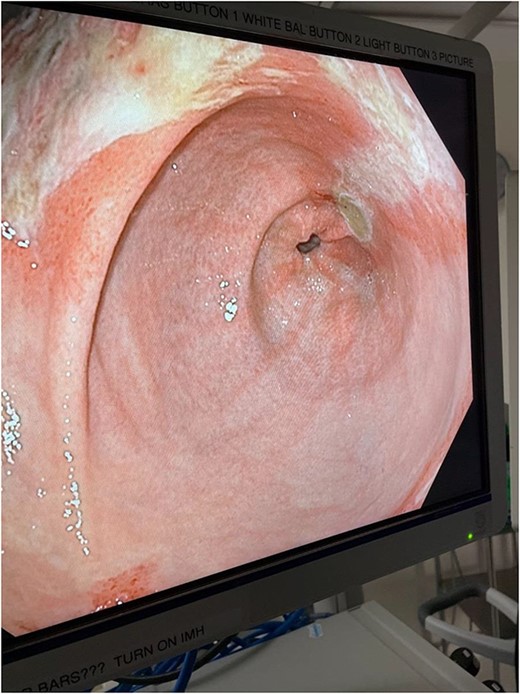

The decision was made to take the patient to the operating room. He underwent diagnostic laparoscopy, which showed a normal gastric antrum; however, on further inspection, a hemorrhagic and inflamed area of stomach was seen proximally at the fundus on the underside of the diaphragm. Next, esophagogastroduodenoscopy was performed, which demonstrated a large black necrotic area in the fundus (Fig. 3), as well as inflammation throughout the rest of the gastric body (Figs 4 and 5). At this point, malignancy could not be ruled out, so the operation was converted to open with a subxiphoid to supraumbilical midline incision. Once in the abdomen and able to further inspect the stomach, the frankly necrotic portion of fundus was noted to be adhered to the underside of the diaphragm and a contained purulent fluid collection was encountered in this area and drained. A partial gastrectomy was then undertaken in similar fashion to a sleeve gastrectomy. The lesser sac was entered and the stomach mobilized along the greater curvature with an energy device up through the short gastrics. A stapler was used to resect the entire necrotic portion of stomach from the midbody to the angle of His. Frozen sections were sent which were negative for malignancy. The remaining stomach was inspected for signs of malignancy, but none were found. For these reasons, no further resection was done. The entire staple line was imbricated due to concern for an ischemic etiology for the patient’s disease process, and two drains were left—one anterior and one posterior to the staple line. Final pathology showed prominent gangrenous necrosis, ulcer and acute necro-inflammatory exudate. Most of the specimen had no viable gastric mucosa, and no malignancy was found.

Intraoperative endoscopic image: inflammatory changes of gastric mucosa in antrum of stomach.